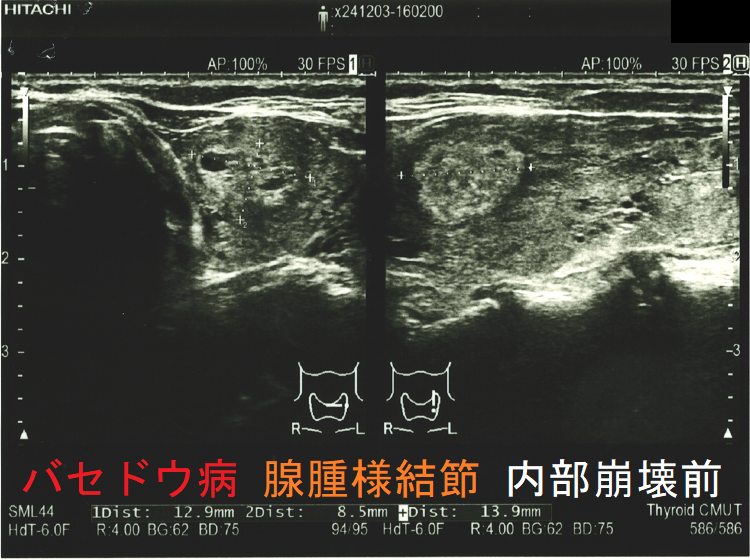

穿刺細胞診後内部融解

ケース①